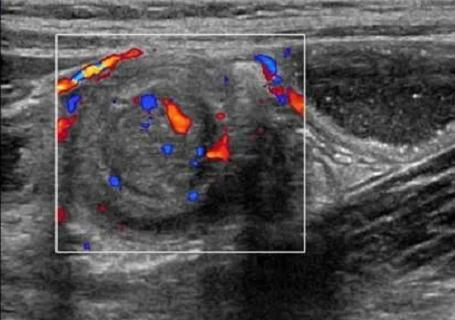

(3)彩色多普勒超声检查可观察肠套叠肿块内部肠系膜是否具备彩色血流信号,发现肿块内部发生的血流动力学变化,腹腔积液情况与透声状态,从而对出血坏死性肠套叠进行排查。